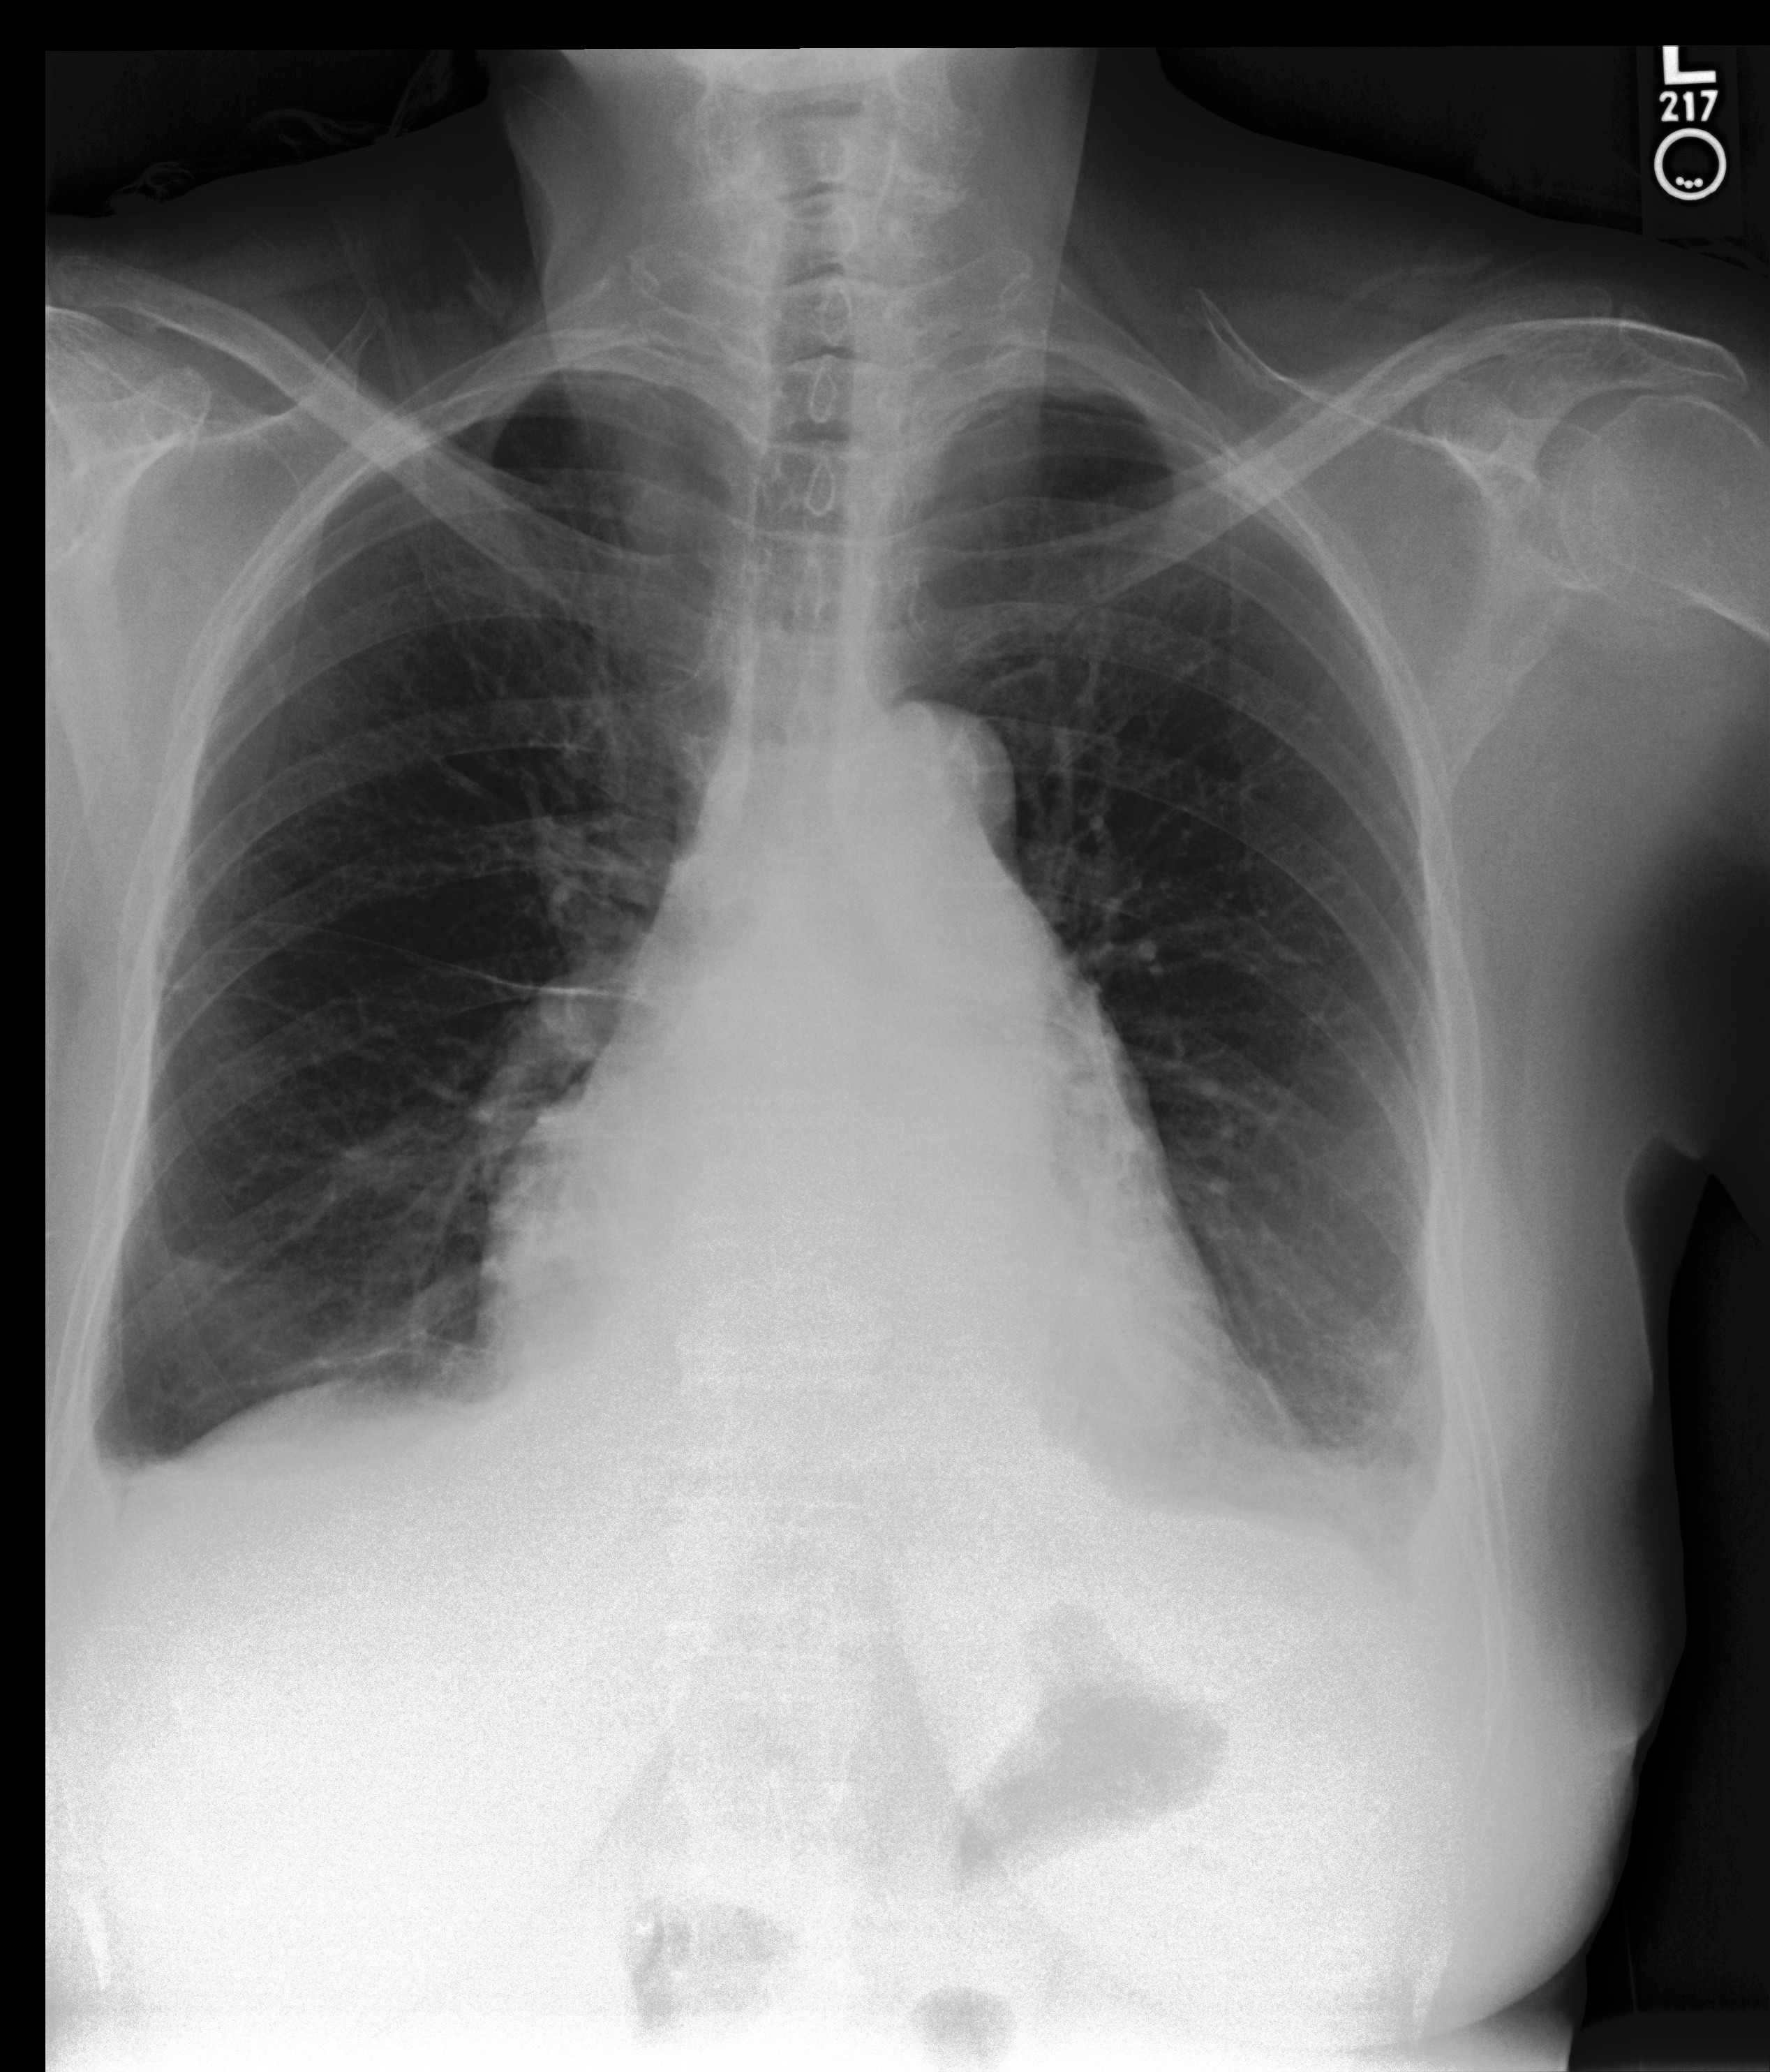

Chest X-Ray Ground Truth Our predictions

[Uncaptioned image] Lungs remain well inflated without evidence of focal airspace consolidation, pleural effusions, pulmonary edema or pneumothorax.Irregularity in the right humeral neck is related to a known healing fracture secondary to recent fall. PA and lateral views of the chest         at 09:55 are submitted. no findings. no pneumonia. no pleural effusion. no edema. there is little change and no evidence of acute cardiopulmonary disease. no pneumonia, vascular congestion, pleural effusion.of incidental note is an azygos fissure, of no clinical significance. this raises possibility of a normal variant.